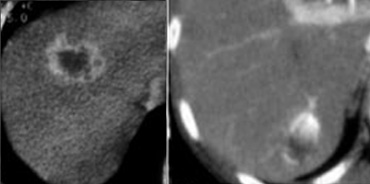

Cholangiocarcinoma: Non enhanced, arterial, portal venous and equilibrium phase. Cholangiocarcinoma: Non enhanced, arterial, portal venous and equilibrium phase.

First look at the images on the left and try to find good descriptive terms for what you see. Then continue.

The lesion on the left has the folowing characteristics:

• The lesion is hypodens in the arterial and portal venous phase with some peripheral enhancement.

• The lesion is hyperdense in the equilibrium phase indicating dens fibrous tissue.

• The lesion causes retraction of the liver capsule

The finding of an infiltrating mass with capsular retraction and delayed persistent enhancement is very typical for a cholangiocarcinoma.

Infiltrative cholangiocarcinoma does not cause mass effect, because when the stroma matures, the fibrous tissue will contract and cause retraction of the liver capsule.

There are not many tumors that cause retraction of the liver capsule, since most tumors will bulge.

The most common tumor that causes retraction besides cholangiocarcinoma is metastatic breast cancer.